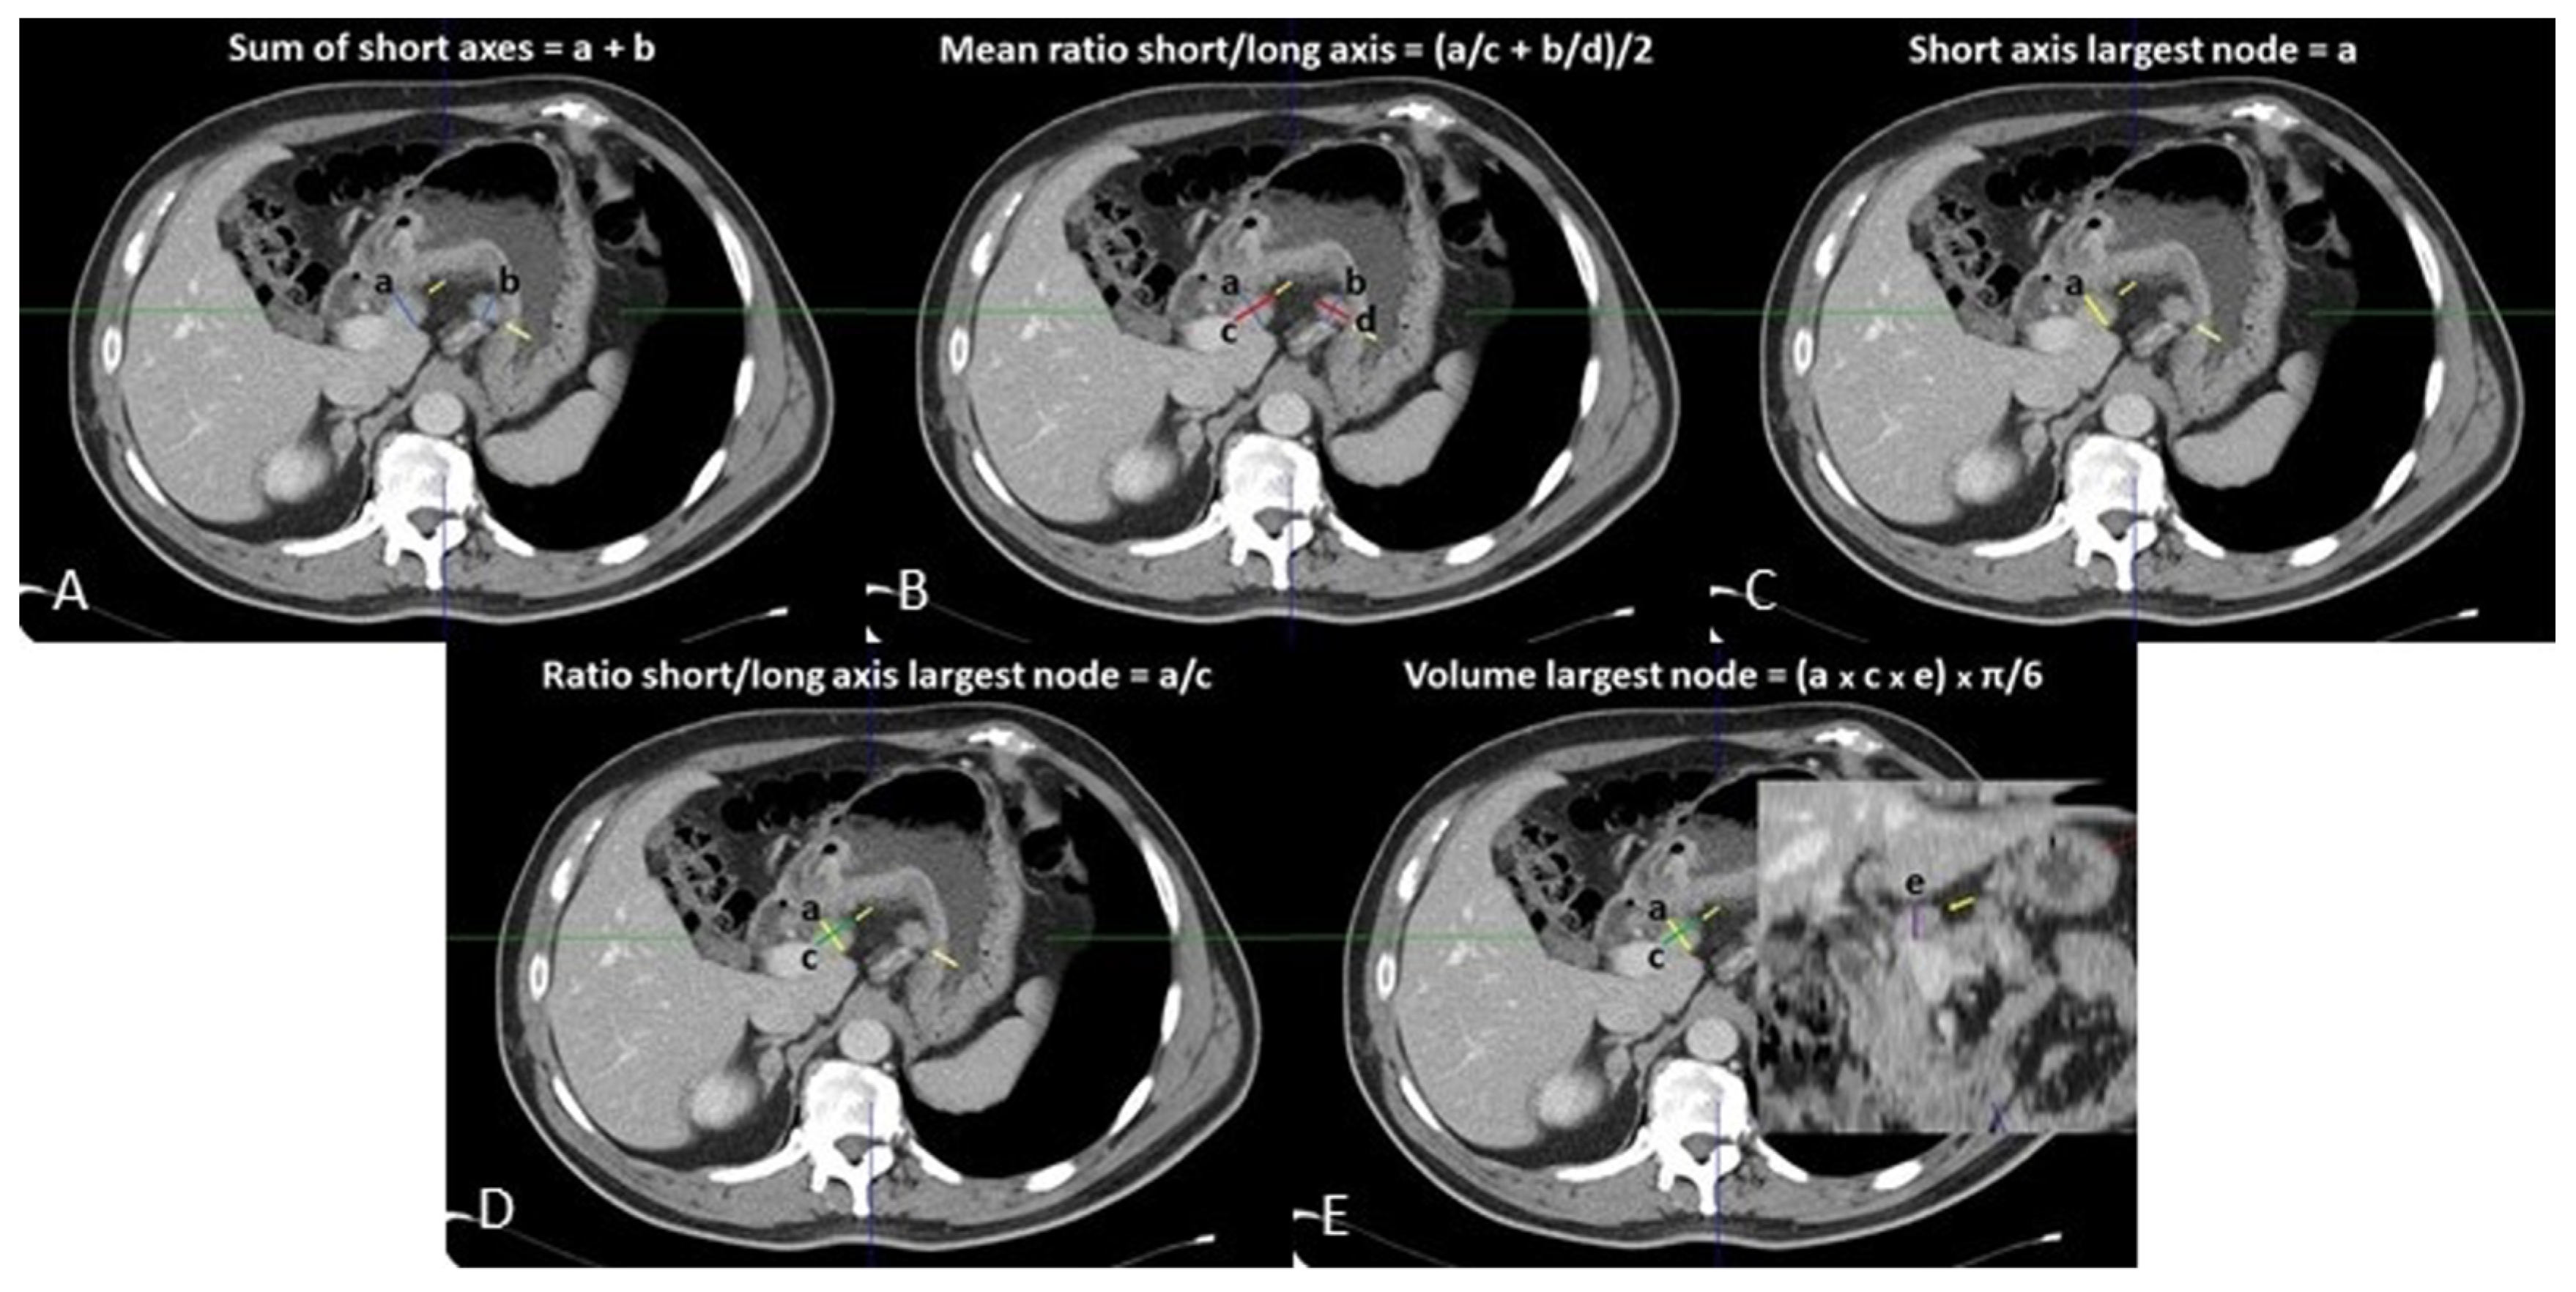

Venous phase images were analyzed on a dedicated workstation (Vitrea2 FX version 6.3, Vital Images, Plymouth, MN, USA). The principal gastric lymphatic stations (paracardial, small and large curve, supra- and sub-pyloric, along left gastric vessels, hepatic artery, celiac trunk, splenic artery, at splenic hilum, retro-pancreatic, and hepato-duodenal) were examined jointly by two abdominal radiologists (with 15 and 5 years of experience), blinded to the pathological diagnosis of the resected LNs. Nodes < 5 mm in maximum size were disregarded. All loco-regional LNs ≥ 5 mm were identified, and their orthogonal axes were measured: the smallest and largest axes on the axial plane were considered as the SA and LA, respectively, while the third measurement obtained was the maximum sagittal axis (Figure 1). The volume of the largest LN per nodal station was calculated according to the formula: SA × LA × sagittal axis × π/6 (mL) (Figure 1).

Figure 1.

Loco-regional CT measurements: (A) sum of short axes; (B) mean of ratios of short/long axes; (C) short axis of largest lymph node; (D) ratio of short/long axis of largest lymph node; (E) volume of largest lymph node.

Five variables per nodal station (the sum of the SAs, the volume, SA, and SA/LA ratio of the largest LN, and the arithmetical average of the SA/LA ratios of all LNs) were recorded in a database. After that, the measurements and the histopathological results of each loco-regional nodal group were reviewed and matched by the two radiologists with the supervision of a dedicated pathologist.